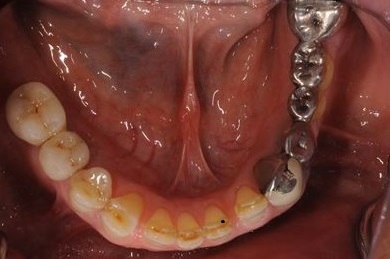

インプラントの症例写真 IMPLANT

骨再生インプラント治療+セラミック治療

| 性別/年齢 | 男性 / 60歳 | ||||||||||||||||||||||||||||||||

| 主訴 | 右上奥歯が動いて痛みがある。 | ||||||||||||||||||||||||||||||||

| 治療内容 | インプラント5本(サイナスリフト、GBR)、ハイブリッドセラミッククラウン5本、メタルボンドセラミッククラウン1本(メタルボンド用土台1本)、ハイブリッドセラミックインレー、遊離歯肉移植手術 | ||||||||||||||||||||||||||||||||

| 治療期間 | 1年7ヶ月 |